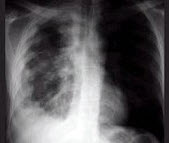

242、单项选择题

男,6岁。经常咳嗽、憋喘,呼吸急促、口唇青紫,进行性加重。X线检查如图,最可能的诊断为()

A.先天性PDA

B.先天性VSD

C.先天性ASD

D.法洛氏四联症

E.先天性肺动静脉瘘